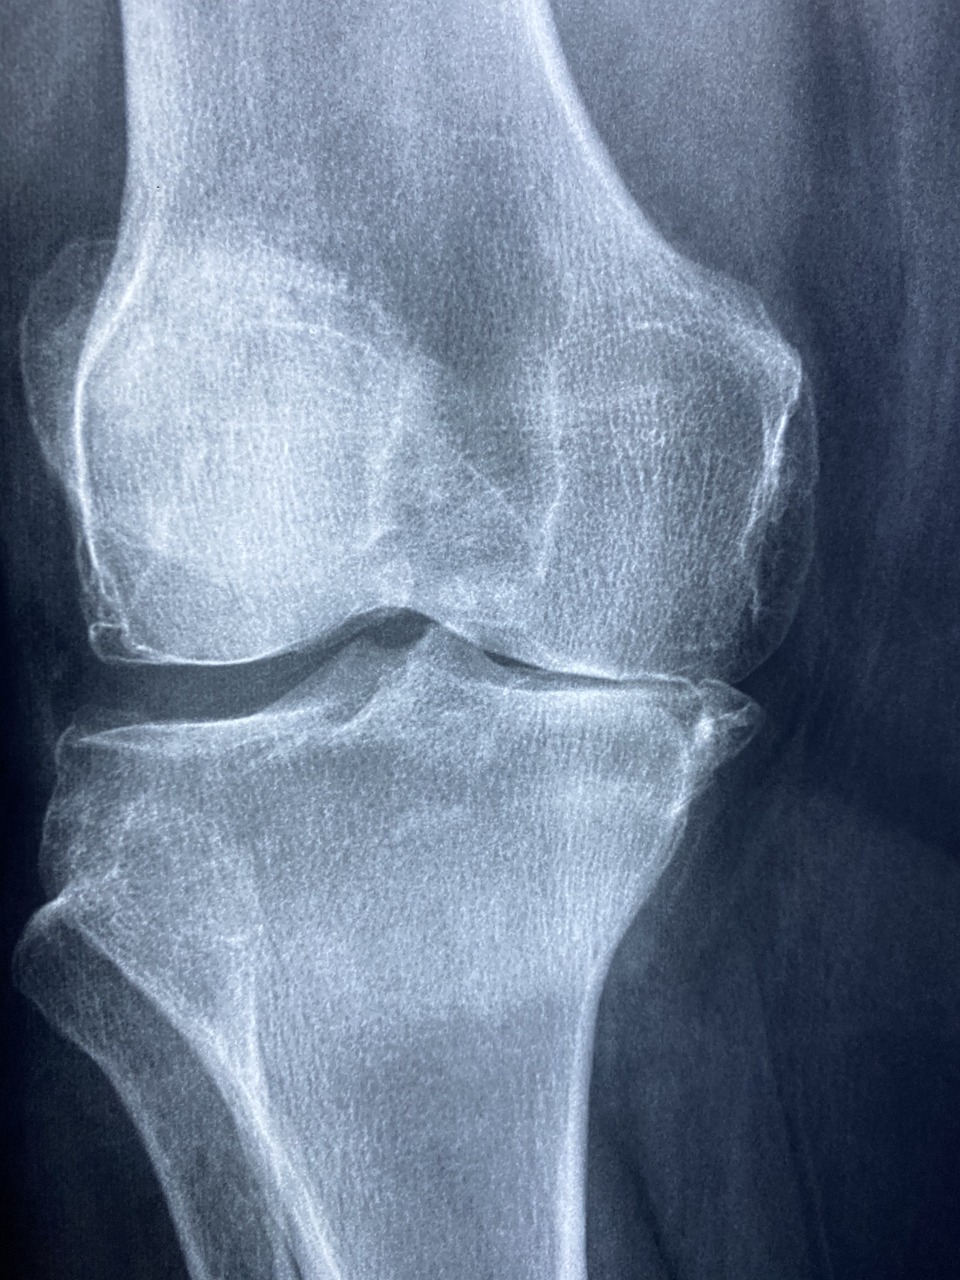

원판형 반월상연골 기형(Discoid Meniscus)은 정상적인 반월상연골보다 크고 둥근 모양을 가진 선천적 기형으로, 주로 외측 반월상연골에서 발견됩니다. 이로 인해 무릎이 걸리는 듯한 느낌, 통증, 부종 등의 증상이 나타날 수 있으며 심한 경우 관절이 불안정해지고 연골 손상이 진행될 수 있습니다.

이 기형은 출생 시부터 존재하지만, 어린 시절에는 증상이 없는 경우가 많습니다. 하지만 성장하면서 운동량이 증가하거나 외상으로 인해 손상이 가해지면 증상이 심화될 수 있습니다. 증상은 주로 무릎이 ‘뚝’ 하고 걸리는 느낌(클릭 현상), 반복적인 무릎 통증, 붓기 등으로 나타납니다.